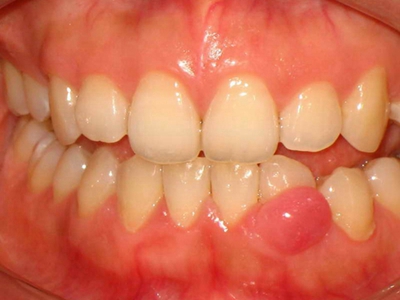

牙龈瘤是指发生在龈乳头部位的炎症反应性瘤样增生物,好发于女性,前磨牙区最为常见。牙龈瘤来源于牙周膜及牙龈的结缔组织,因其无肿瘤的生物学特征和结构,故非真性肿瘤,但切除后易复发,因此切除务必彻底,必要时拔除相关牙齿。

牙龈瘤多发于女性,以青年及中年人为常见,多发生于牙龈乳头部,位于唇、颊侧者较舌、腭侧者多,最常见的部位是前磨牙区。肿块较局限,呈圆形或椭圆形,有时呈分叶状,大小不一,直径由几毫米至数厘米。

肿块有的有蒂,如息肉状;有的无蒂,基底宽广,生长较慢,但在女性妊娠期间可能迅速增大。较大的肿块可以遮盖一部分牙及牙槽突,表面可见牙压痕,易被咬伤而发生溃疡,伴发感染。随着肿块的增长,牙槽骨壁逐渐被破坏,牙可能发生松动、移位。